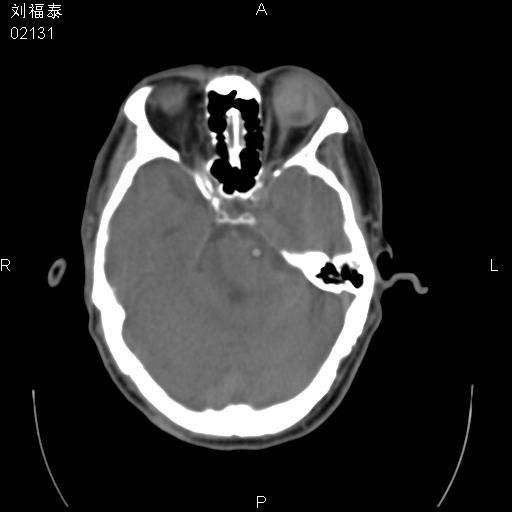

以下是引用余辉在2008-3-4 14:00:00的发言:[br]考虑左眼球黑色素瘤或血管源性肿瘤可能性大,建议增强检查

以下是引用余辉在2008-3-4 14:00:00的发言:[br]考虑眼球黑色素瘤或血管源性肿瘤可能性大,建议增强检查

以下是引用zsl6918在2008-3-4 15:08:00的发言:[br]现有征象只能提示球内出血,视网膜脱落,至于是否为肿瘤性病变需mri检查。